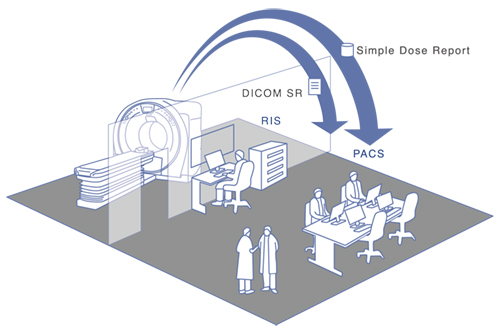

Simple Dose Report / DICOM SR

線量情報をセカンダリーキャプチャー画像として,PACSに送信したり,DICOM構造化レポート(DICOM SR)として,PACSなどへ送信することも可能です。